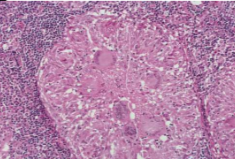

Histopathology: malignant epithelial cells and islands seen in underlying connective tissue